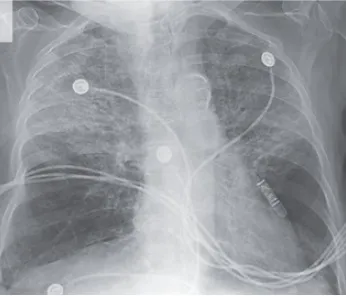

IRA + Icterícia: Um Caso que Exige Investigação Detalhada